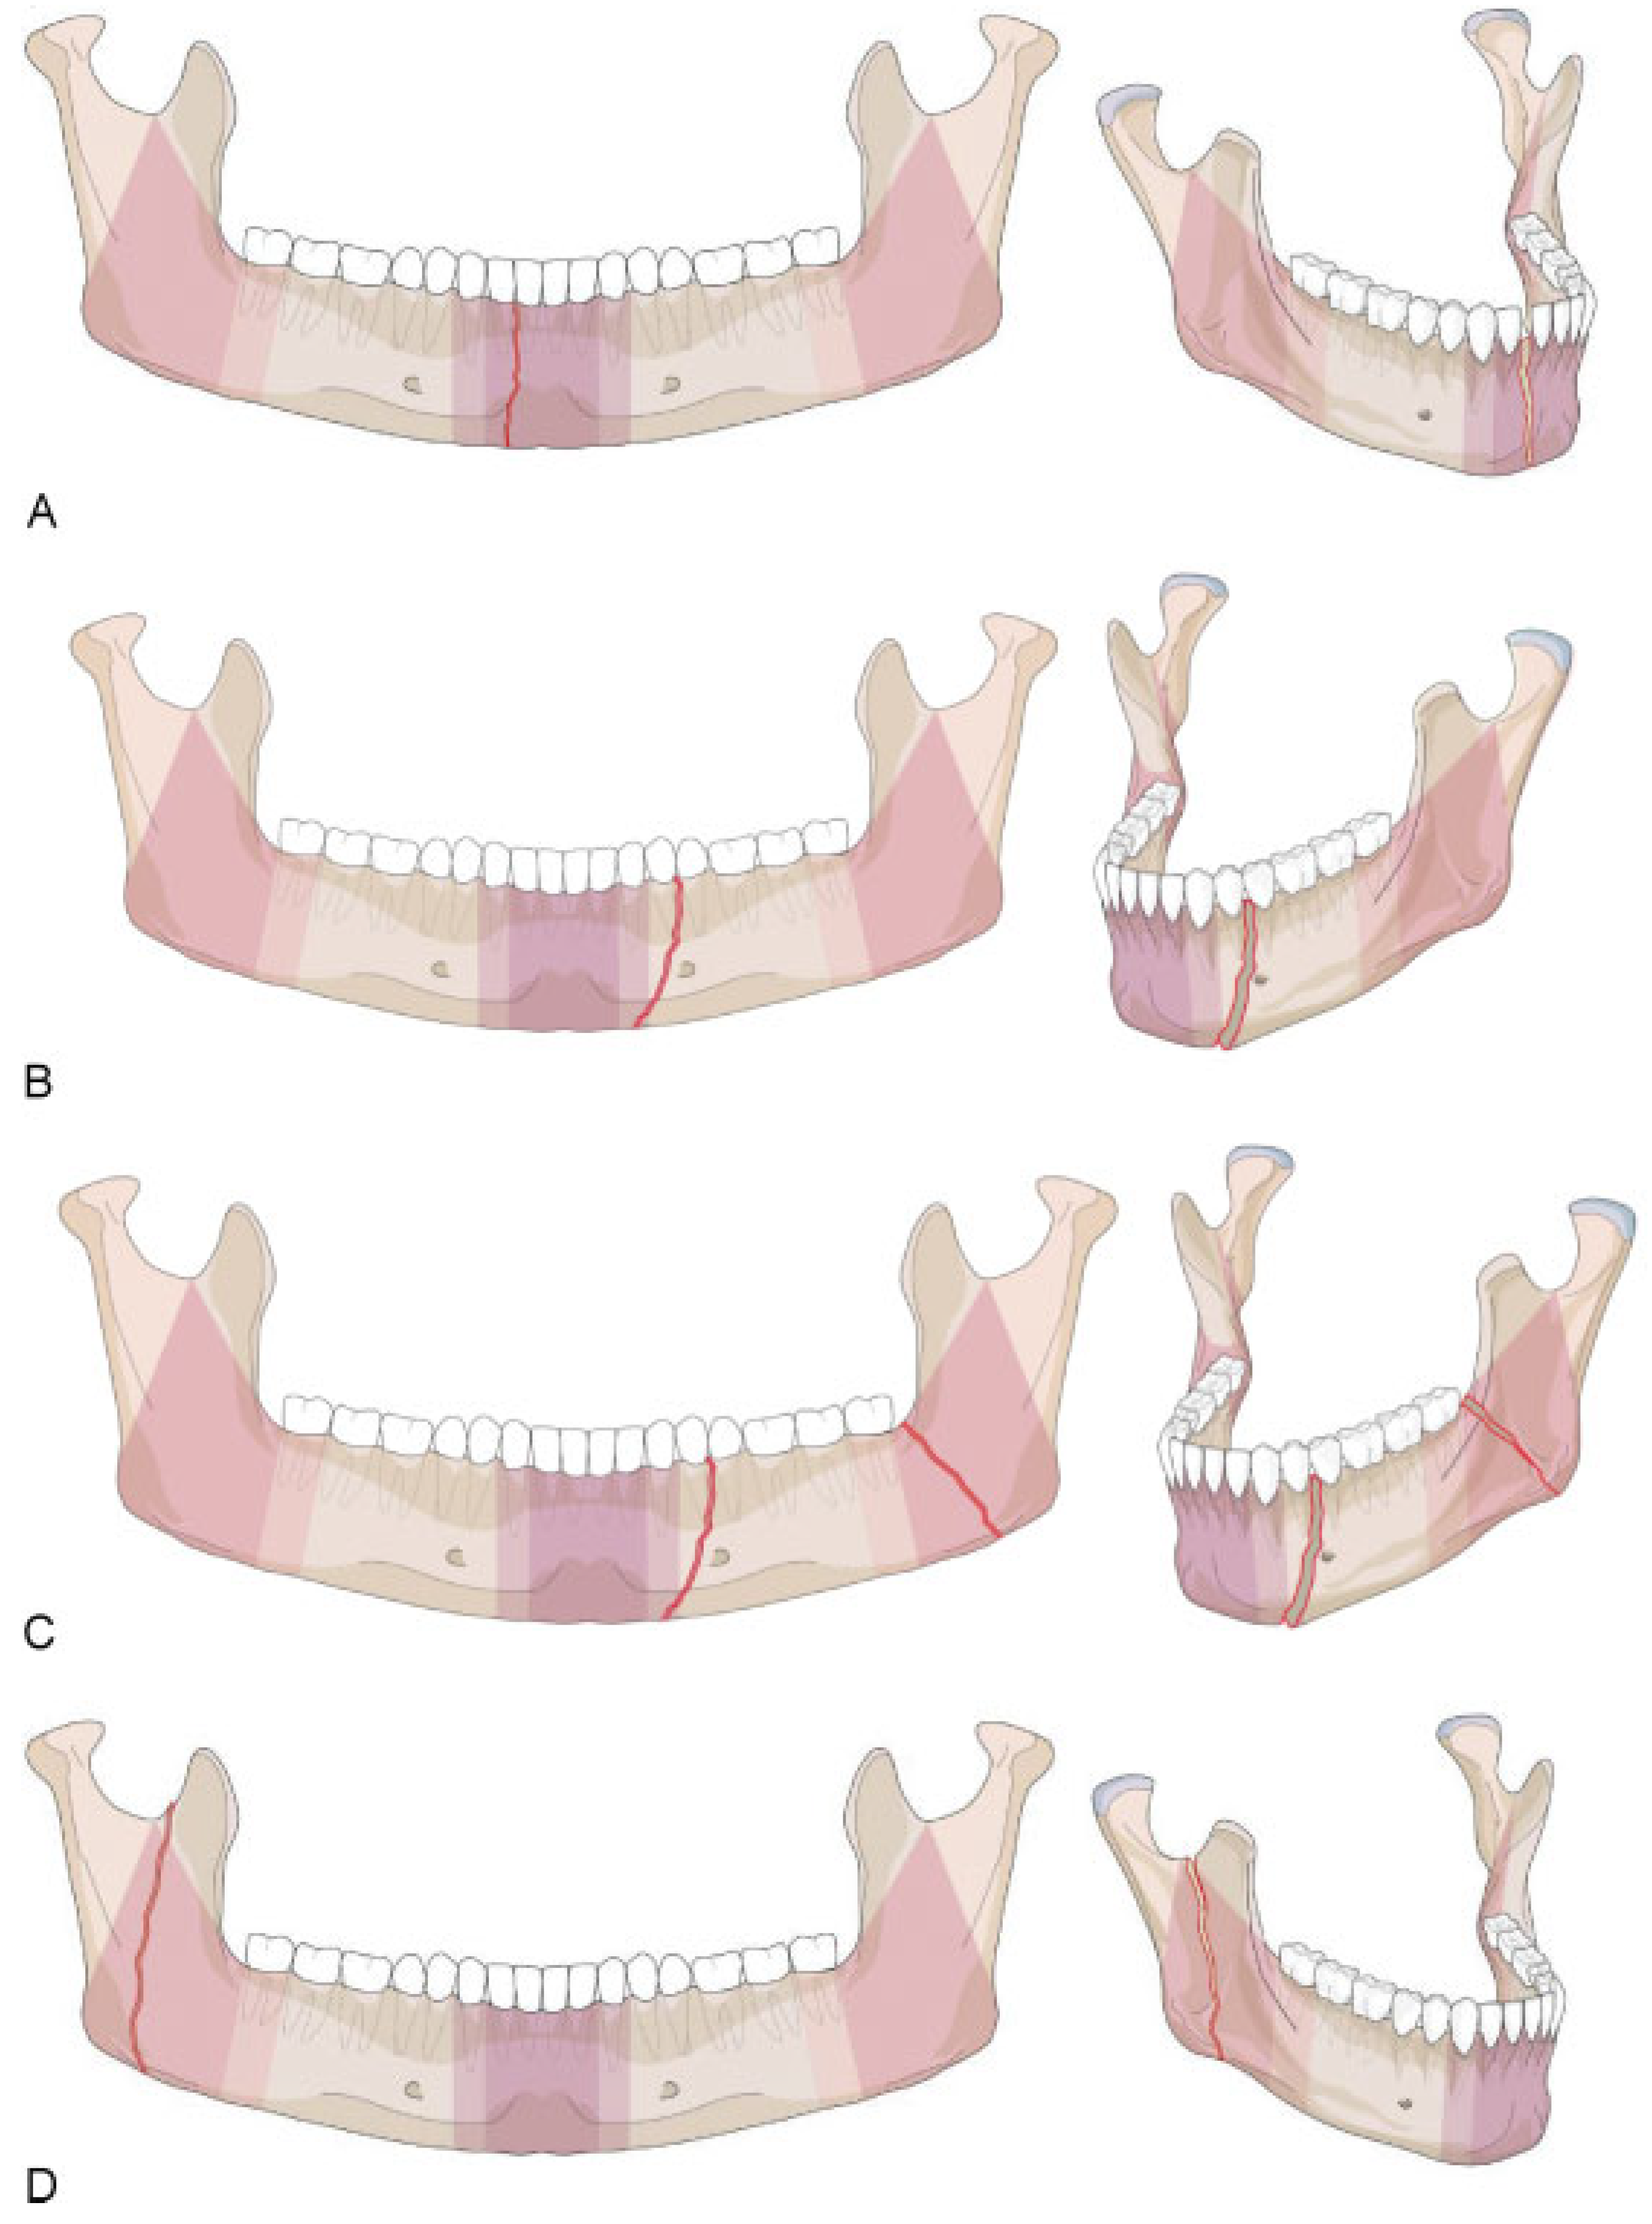

Symphysis/Parasymphysis Region

Mandibular Body Region

Angle/Ramus Region

Confinement—Fractures Located within Anatomical Regions

- • “Confined” fracture pattern: the fracture, irrespective of its morphology, remains within an anatomical region (including a transition zone) and does not extend into an adjoining region across a transition zone.

- • “Nonconfined” fracture pattern: the fracture crosses at least one transition zone and may extend over one or more adjoining region.